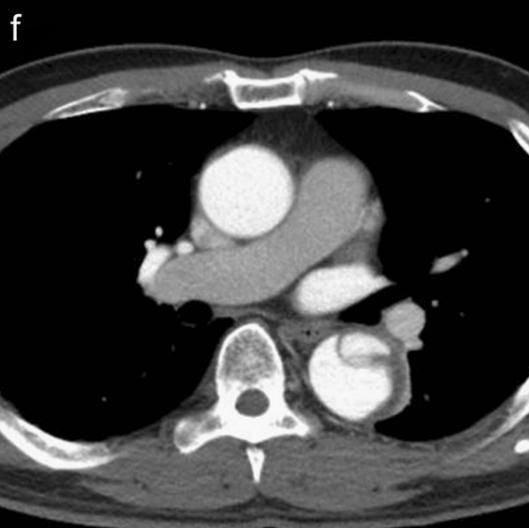

病例4

下图的胸部CT平扫,基本上大约肯定可以看到一条线样阴影,将主动脉一分为二!

图10

增强CT一看,主动脉裂开了!

图11